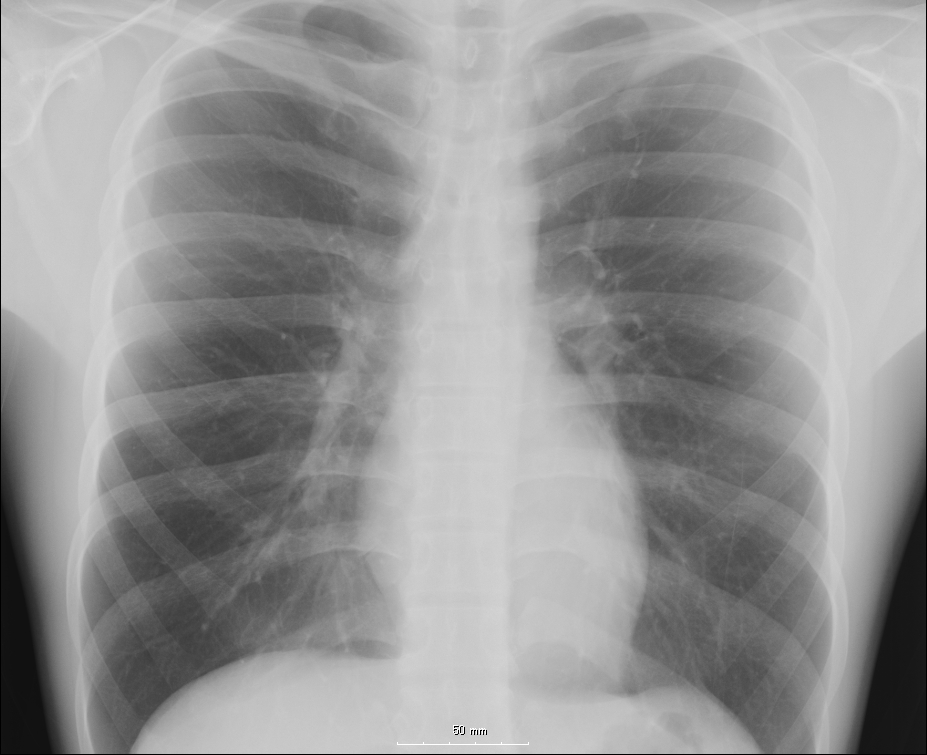

Doctors whose bodies are regularly exposed to x-rays may be adapting at the cellular level to protect themselves against radiation, according to a new study. The research hints that humans could adapt to withstand radiation exposure.

Interventional cardiologists receive a higher annual radiation dose than radiologists, because of the way they do their work. A patient is exposed to high radiation levels so the doctor can see the catheter they’re using to perform certain minimally invasive heart procedures. To do this, the cardiologist has to work close to the radiation source. These x-ray guided procedures have nearly doubled from 1993 to 2006, the researchers report — meaning the relatively small doses add up over time.